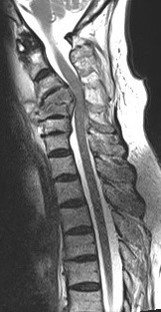

Ameliyat Öncesi